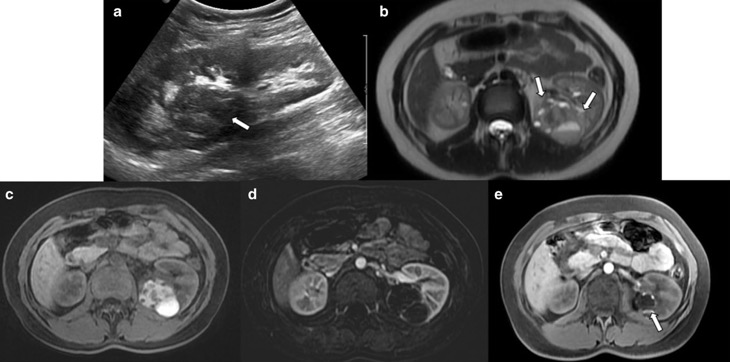

4. Pseudotumeurs rénales diverses

- Rein cicatriciel avec nodules de régénération

- Kyste rénal hémorragique